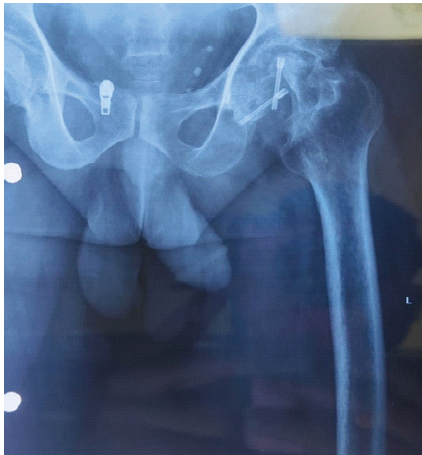

A male patient in his early 30s presented with progressively worsening left hip pain over the past 6 months, significantly limiting his mobility and ability to bear weight through his prosthetic limb. Three years earlier, he had sustained multiple injuries in a high-impact road traffic accident, necessitating a low AKA on the left side. At that time, he also sustained a fracture of the ipsilateral femoral neck, for which he underwent safe surgical dislocation and internal fixation using headless screws. Post-operatively, he achieved initial recovery and was ambulatory with a prosthesis. However, over time, he developed a persistent, dull ache in the left hip, which intensified and became disabling. On examination, the stump was well-healed with no signs of infection or contracture, but notable gluteal muscle wasting and severe, painful restriction in hip range of motion were present. Pelvic radiographs demonstrated advanced arthritis of the left hip (Tönnis Grade 3), with femoral head collapse and retained headless screws in situ (Fig. 1). Pre-operative functional assessment using the Harris hip score (HHS) was 30, indicating severe disability [9].

Figure 1: Pre-operative radiograph.

A full-length radiograph of the residual stump was obtained for templating. The residual stump was long with minimal thinning of the cortices and widening of the medullary cavity. Non-contrast computed tomography of the pelvis was done to rule out any heterotopic ossification. A DEXA scan of the proximal femur region ruled out osteoporosis. Other basic pre-operative and infective workup revealed no significant abnormality.